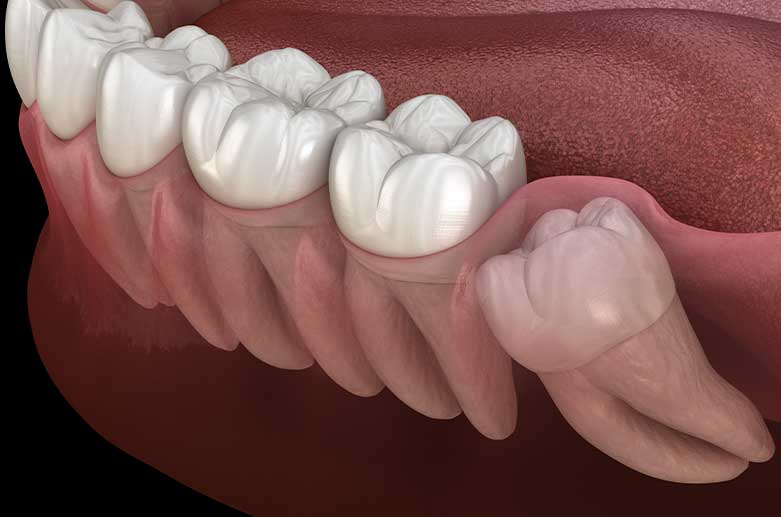

Wenn die Weisheit mal verquer sitzt… gerne beraten wir Sie bei allen Fragen rund um Ihre Weisheitszähne und/oder Kieferknochenschwund.

Eine gründliche Anamnese, professionelle Aufklärung und Nachsorge sind bei einfachen wie bei komplexeren operativen Eingriffen bei uns Standard. Durch präzise, minimalinvasive Chirurgie und unter Lokalanästhesie, können wir Ihnen alle vorhandenen Weisheitszähne in nur einer Sitzung in unserer Zahnarztpraxis entfernen. Auch Risiko- und Angstpatienten können in unserer Praxis behandelt werden.